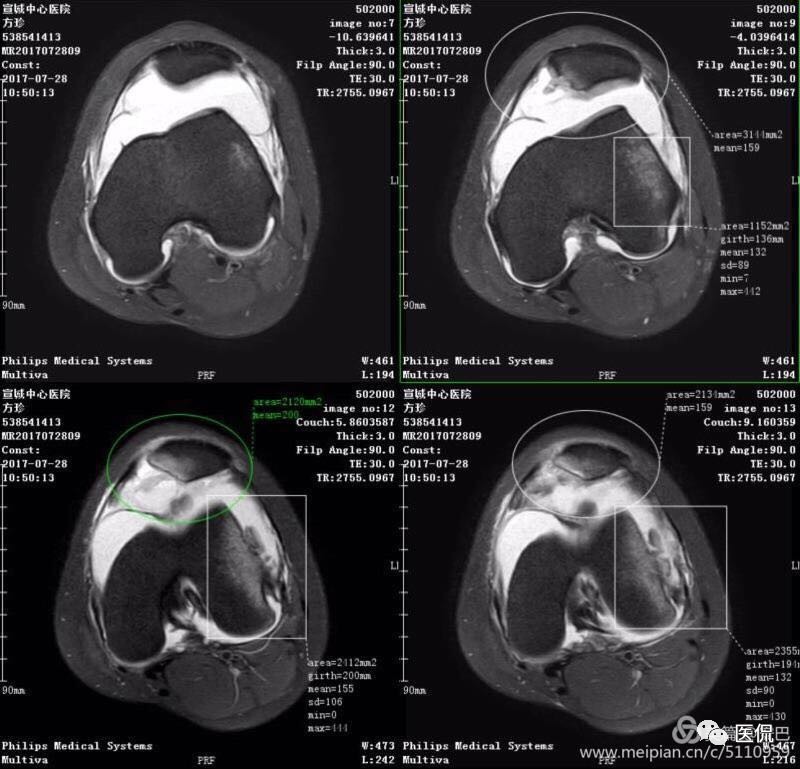

MR表现

1、单液-液平面:上层呈短T1、长T2信号、T2压脂像低信号、Pd像呈高信号;下层呈中等T1、T2信号、T2压脂像和Pd像呈较高信号。

2、双夜-液平面:上层呈短T1、长T2高信号、T2压脂像低信号、Pd像呈高信号;中层呈长T1、长T2信号、T2压脂像和Pd像呈较高信号;下层呈中等T1、T2信号、T2压脂像和Pd像呈较高信号。

3、多液-液平面:最上层呈无信号区;上层呈短T1、长T2高信号、T2压脂像低信号、Pd像呈高信号;中层呈长T1、长T2信号、T2压脂像和Pd像呈较高信号;下层呈中等T1、T2信号、T2压脂像和Pd像呈较高信号。

创伤性关节积脂血症MR影像表现的意义

1、通过不同成像序列及不同扫描方位成像,不仅能够准确地显示单液-液平面、双液-液平面和多液-液平面,明确地诊断创伤性关节积脂血症,且在关节创伤的不同时期,由于血液中的成分不同,MRI显示的信号也有改变,可以用于估计受伤时期。

2、显示关节囊内骨折、软骨骨折、骨挫伤。

3、同时又能判断交叉韧带、侧副韧带、肌腱以及半月板的损伤。